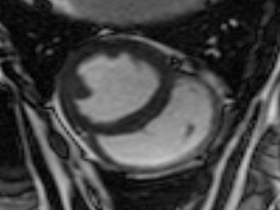

Easy-Trigger ist ein Medizinprodukt für die Herz- und Gefäßbildgebung in der Magnetresonanztomographie (MRT), das bifunktional bei Ungeborenen und Erwachsenen eingesetzt werden kann. Als weltweit erstes und einziges MRT-taugliches Doppler-Ultraschallgerät ermöglicht es erstmals Kombinationsuntersuchungen von MRT und Ultraschall. Der Ultraschallkopf wird auf dem Bauch oder über dem Herzen des Patienten platziert. Es ermöglicht erstmals die zeitliche Abstimmung der Herzaktion von ungeborenen Kindern mit dem MRT und damit MRT-Untersuchungen des kindlichen Herzens. Des Weiteren kann es zur Überwachung der Ungeborenen bei MRT-Untersuchungen von Schwangeren eingesetzt werden. Durch die Verwendung der Doppler-Ultraschall-Technik ist die Anwendung am Erwachsenen im Vergleich zum EKG robuster, einfacher und sogar bei höheren Feldstärken einsetzbar, bei denen das EKG nicht mehr zuverlässig arbeitet.

Cardiac MRI of the Fetal Heart Using a Novel Triggering Method: Initial Results in an Animal Model.

J Magn Reson Imaging. 2012 May;35(5):1071-6.